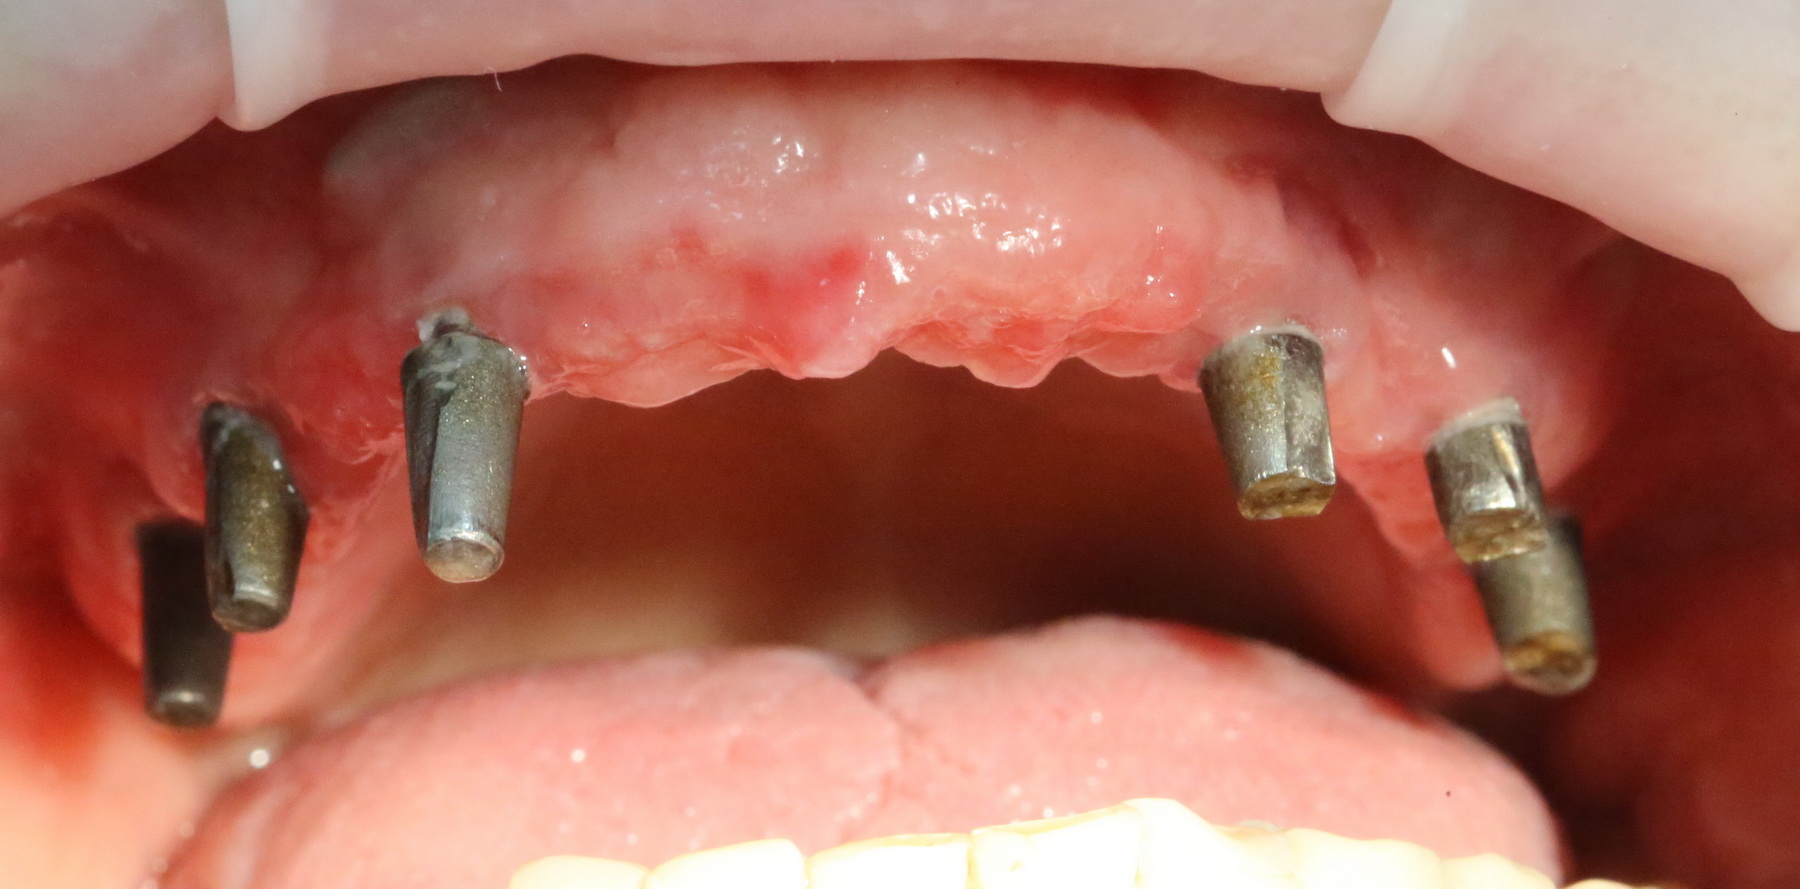

и, периодически, мне приходится видеть пациентов с базальными имплантами:

Как правило, вся работа с этими имплантами сводится к их удалению:

К слову сказать, базальные импланты не интегрируются, а удерживаются, исключительно, за счет своей формы:

А это значит, что длительная функциональная нагрузка в таком объеме просто будет их медленно расшатывать. Особенно, если учесть, что их нагружают почти сразу после установки. И весьма большой протетической конструкцией.

И вот, у этой пациентки все импланты, а их, ни много, ни мало, восемь штук, подвижны:

Мы вынуждены их удалить. И теперь представьте, как будет проходить такое удаление и с каким дефицитом костной ткани мы, в итоге столкнемся. Что вообще делать дальше? Девушка плачет.